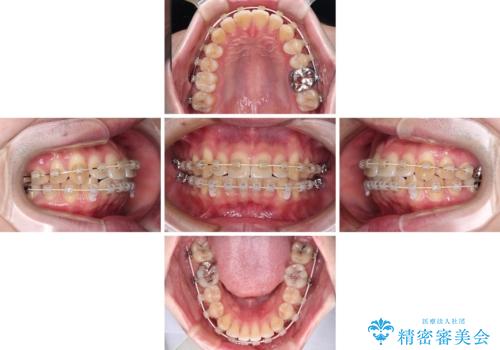

- 上下前歯のデコボコを気にして来院された患者様です。

マウスピース矯正でもワイヤー矯正でも対応可能でしたが、インビザラインによる自己管理が煩わしいとのことで、ワイヤー装置にて矯正治療を行うこととしました。

口元はやや突出感がありましたが抜歯矯正をするほどではないため、舌突出癖を改善するトレーニングをしっかりと行っていただき、現在よりも唇が閉じやすい位置に仕上げていくこととしました。

下顎前歯が思っていた以上に動きが悪く、想定よりも期間がかかってしまいました。